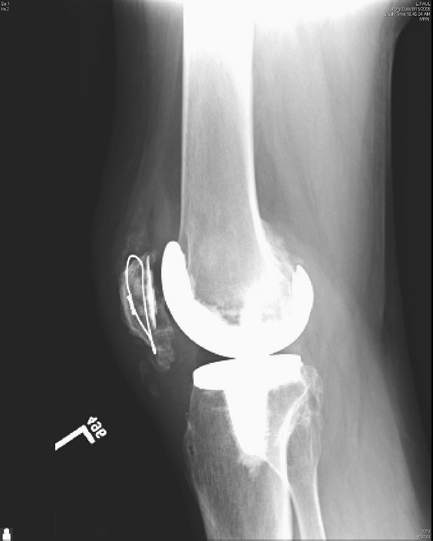

extensor mechanism. Figure 26-1 shows an open

reduction internal fixation of a type II fracture with complete rupture

of the extensor mechanism. Intraoperatively, it was felt that the

remaining distal pole of the patella was large enough for fixation; it

ultimately healed without an extension lag or quadriceps weakness (Figs. 26-2, 26-3, 26-4).

Figure 26-1 Fracture of the inferior patella pole with complete extensor mechanism disruption.